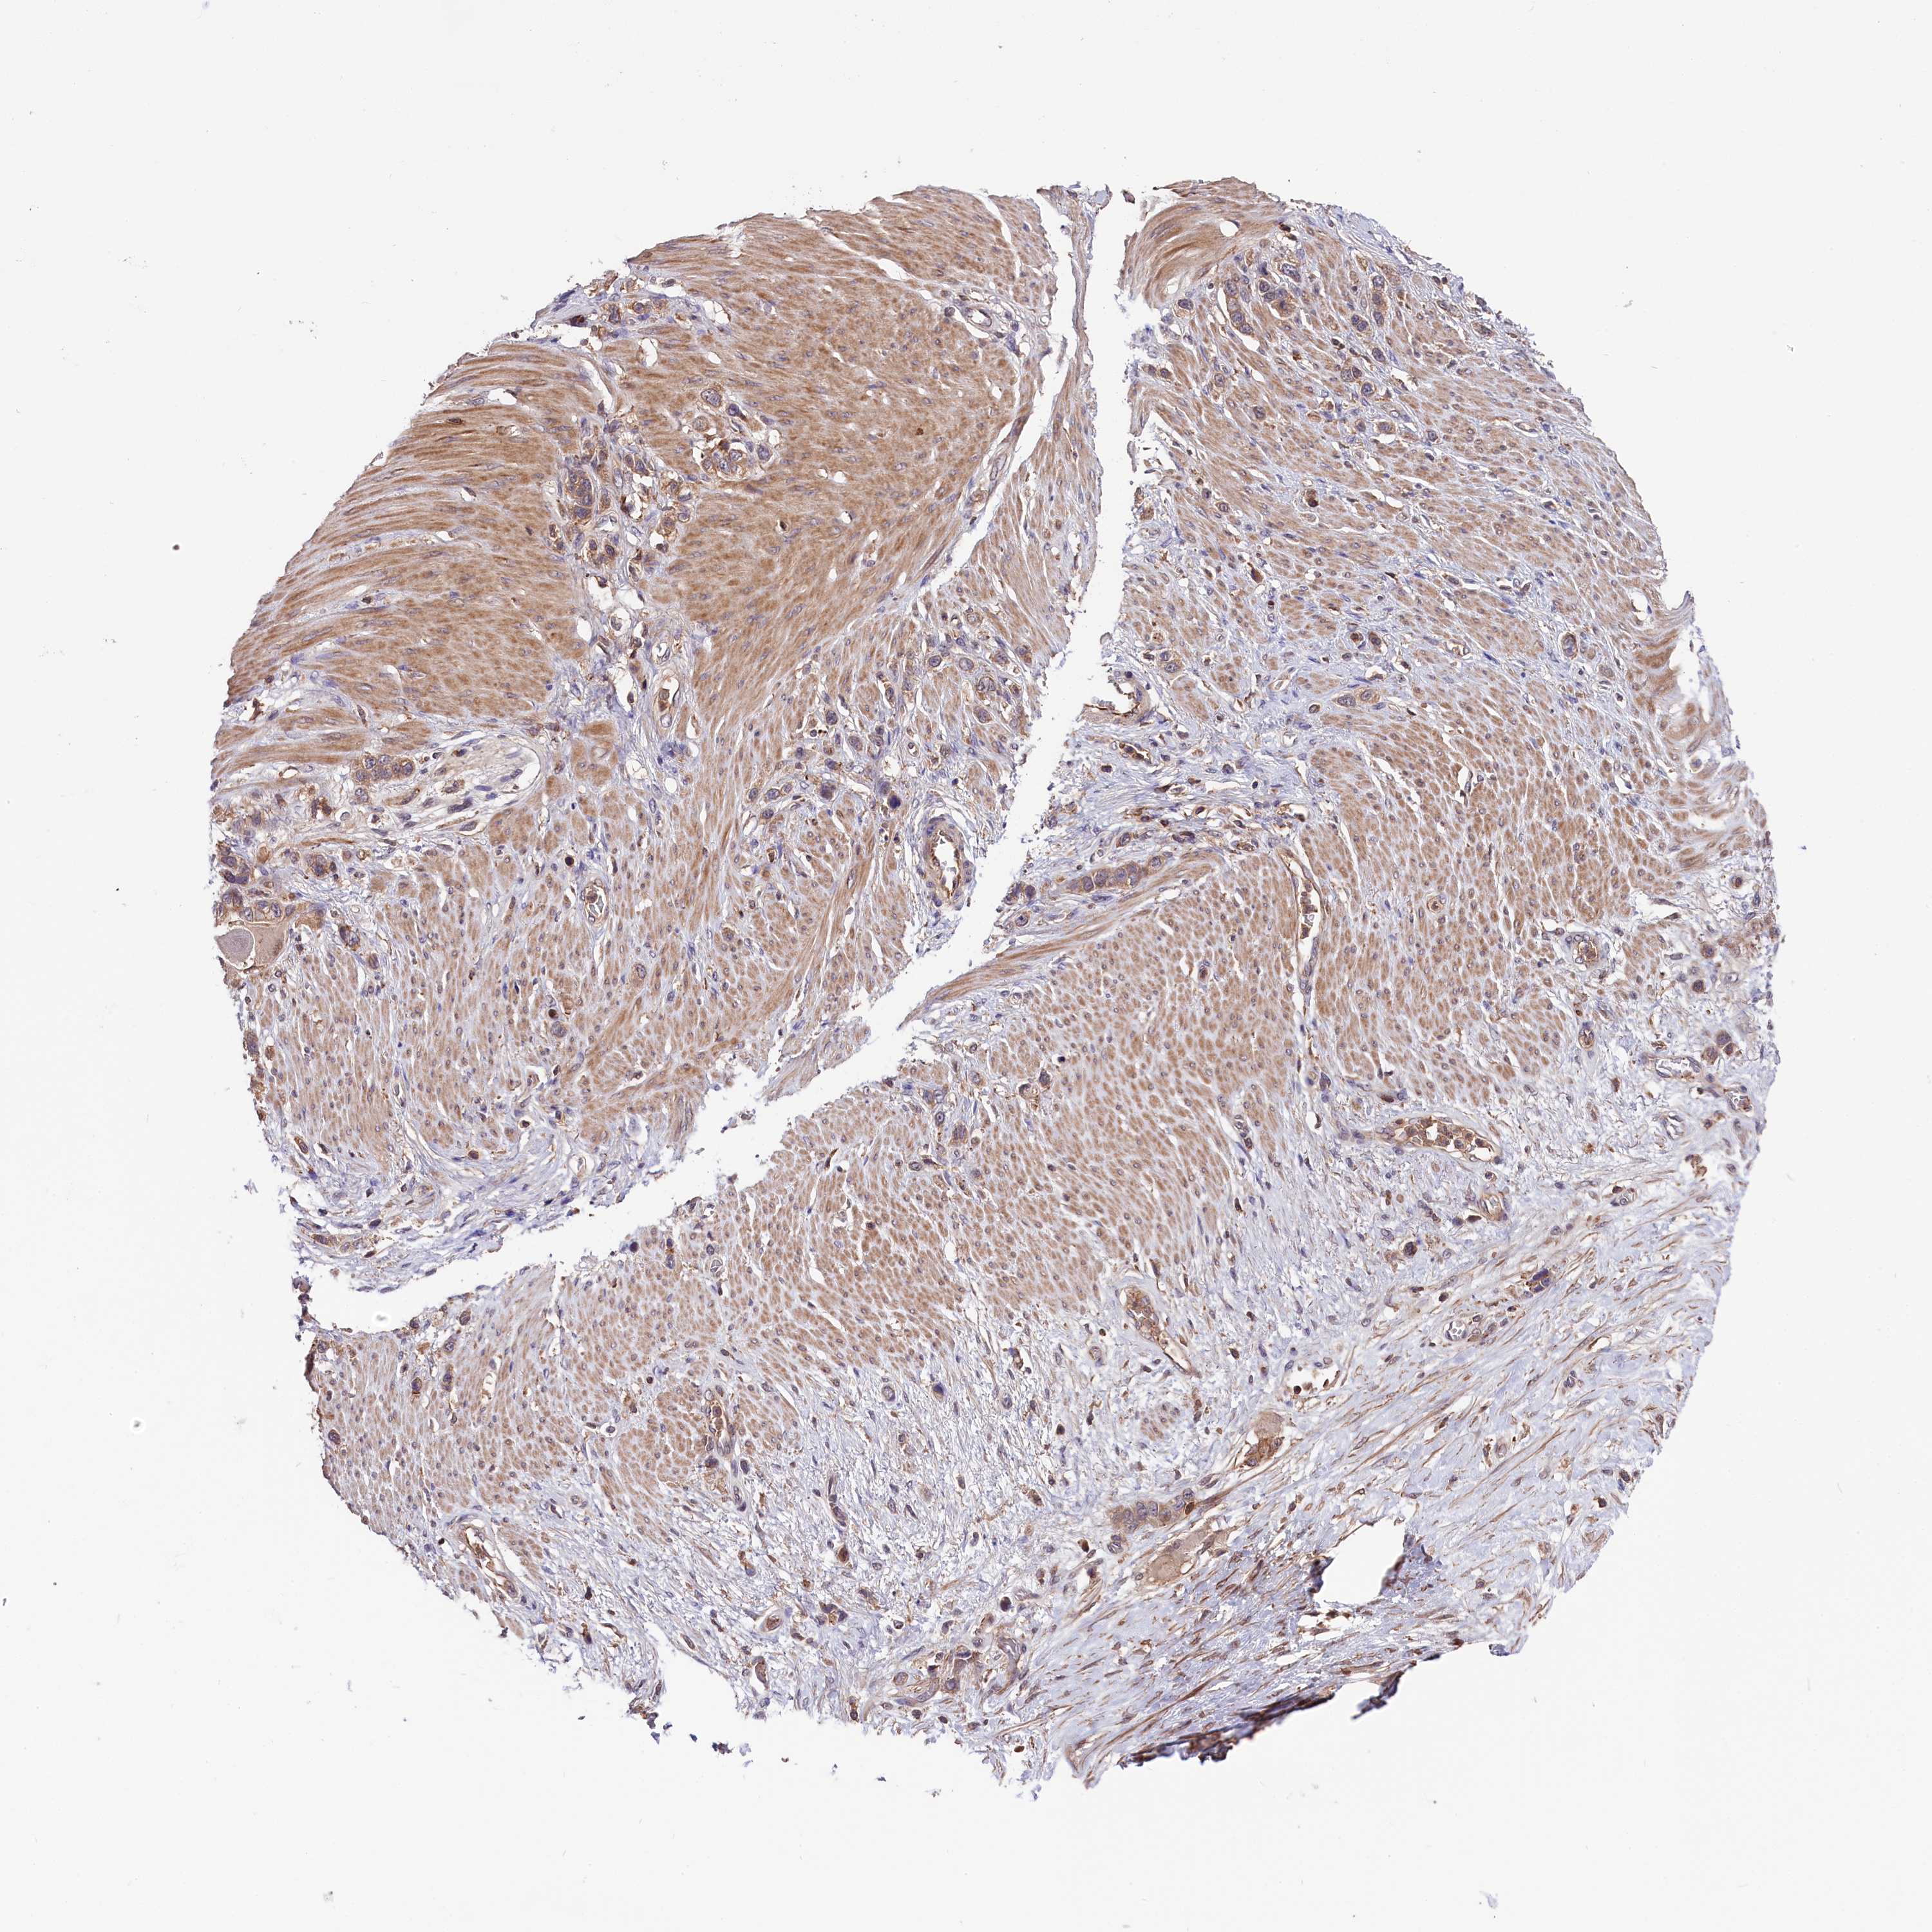

STOMACH CANCER - Protein expressioni

A mouse-over function shows sample information and annotation data. Click on an image to view it in a full screen mode. Samples can be filtered based on level of antibody staining by selecting one or several of the following categories: high, medium, low and not detected. The assay and annotation is described here.

Note that samples used for immunohistochemistry by the Human Protein Atlas do not correspond to samples in the TCGA dataset.

Antibody stainingi

Antibody staining in the annotated cell types in the current human tissue is reported as not detected, low, medium, or high, based on conventional immunohistochemistry profiling in selected tissues. This score is based on the combination of the staining intensity and fraction of stained cells.

Each image is clickable and will lead to virtual microscopy that enables deeper exploration of all samples and also displays staining intensity scores, fraction scores and subcellular localization as well as patient and tissue information for each sample.

Antibody HPA039208

Antibody HPA040439

Staining

High

Medium

Low

Not detected

Intensity

Strong

Moderate

Weak

Negative

Quantity

>75%

75%-25%

<25%

None

Location

Nuclear

Cytoplasmic/membranous

Cytoplasmic/membranous,nuclear

Adenocarcinoma, NOS

Adenocarcinoma, High grade